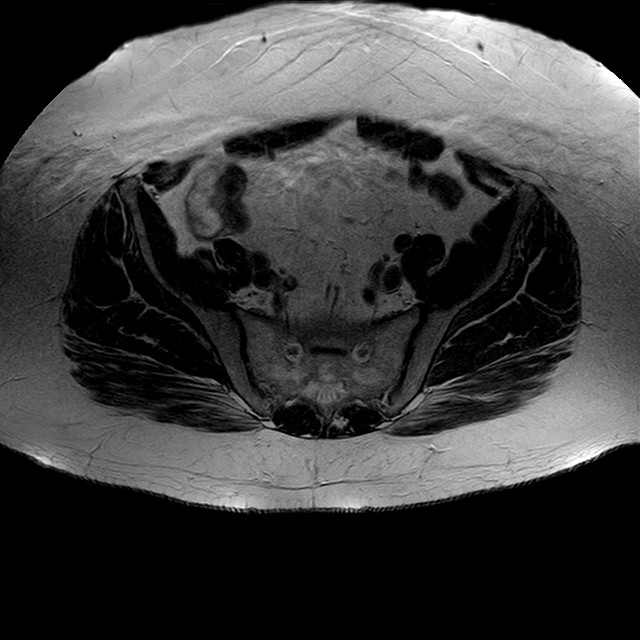

Esami: RMN BACINO

eT2w TSE

Evidenti e simmetriche alterazioni osteofitosiche in regione coxo femorale con riduzione delle rime articolari. Degenerazione completa del cercine glenoideo. Non attuali segni di versamento articolare. Non segni di edema osseo che escludono attuale algodistrofia od osteonecrosi. Lieve e simmetrica riduzione del trofismo della muscolatura glutea.